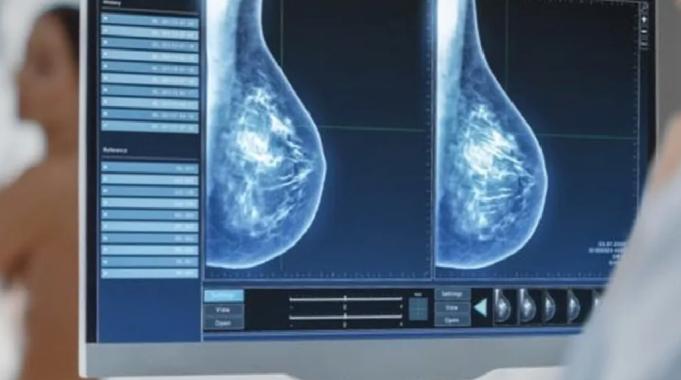

Dr. Güler, meme kanserinin erken teşhis ile tedavi edilebilecek bir hastalık olduğunu belirterek, 50 yaş üzeri kadınların her yıl mamografi yaptırmasının önemine dikkat çekti. Güler, “Kötü haber alırım korkusu nedeniyle mamografi taramalarına girmeyen kadınlarımız var. Bu korkuyu aşarak erken tanı ile hayatlarınızı kurtarabilirsiniz. 40-50 yaş arasındaki kadınlar da doktorlarına danışarak mamografi sıklığını belirlemelidir. Unutulmamalıdır ki erken teşhis hayat kurtarır” diye konuştu.